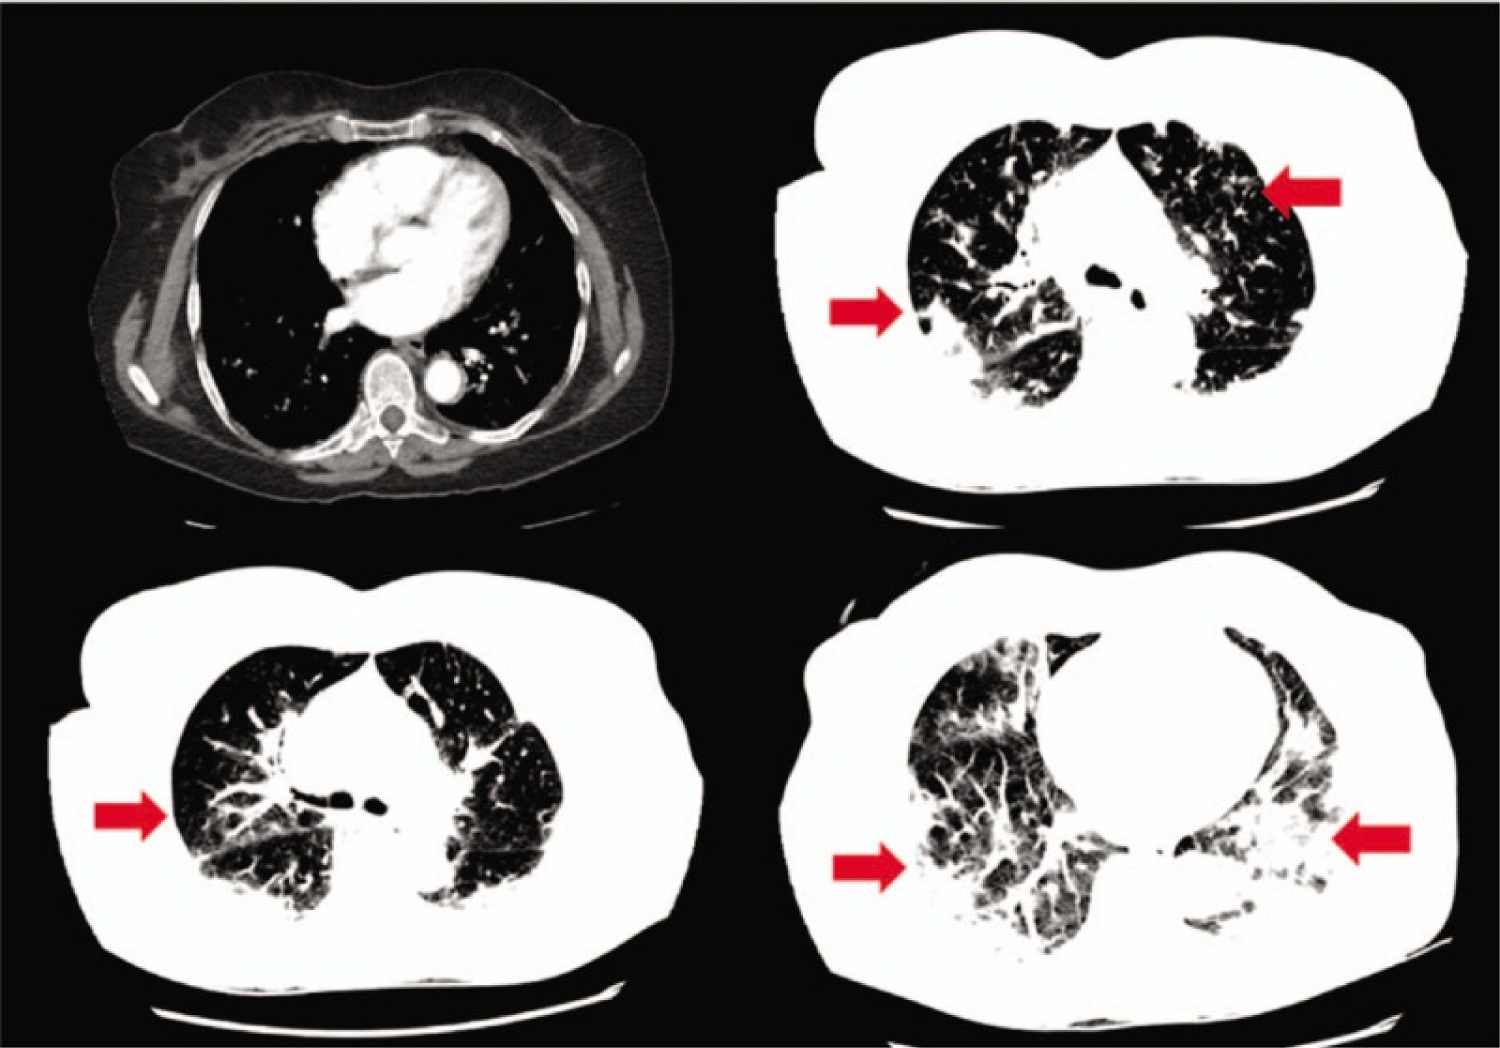

A 77-year-old Middle-Eastern female with a medical history of hypertension and hyperlipidemia presented to the emergency department (ED) from a day care facility apartment where 2 people at the facility have tested positive for COVID-19 but she did not have any direct contact with these individuals. About 5 days before admission the patient developed a fever with a temperature of 102 ℉ at home, and went to her primary medical doctor who sent her to the ED. In the ED she was found to have bilateral opacities on chest X-ray and had continued intermittent fevers with generalized weakness, cough, lethargy, and dyspnea and was sent for testing for COVID-19 then transferred to our facility for further management. In our facility, her temperature was 101.7 ℉, blood pressure 148/76 mmHg, heart rate of 99 beats per minute, respiratory rate of 18 per minute, and oxygen saturation of 93% on room air. Physical exam was significant for a dry cough and bilateral rales on auscultation of the lung fields bilaterally but was unremarkable otherwise. A chest X-ray (Figure 2) was performed showing bilateral opacities throughout the lung fields with predominance of the lower lung lobes she was admitted for possible pneumonia with isolation precautions for suspected COVID-19 and was started on oxygen via nasal cannula and on 1-gram ceftazidime intravenously every 8 hours and 500 mg azithromycin orally daily. CT scan of the chest (Figure 3) was performed showing bilateral ground glass appearance throughout the lung with predominance in the peripheral lower lobes. Respiratory viral panel was sent including a repeat COVID-19 test (Table 2). All results came back negative however the patient's condition deteriorated 2 days after admission to our facility, and she became hypoxic to 85% oxygen saturation while on nasal cannula and remained spiking fevers up to 103.4 ℉. She was intubated and transferred to the intensive care unit (ICU) for further management and was switched to ceftriaxone 1g intravenously daily and azithromycin 500 mg via orogastric tube daily and was started on hydroxychloroquine 400  mg loading dose followed by 200  mg twice daily for a 7-day course. She required 100% fraction of inspired oxygen (FiO2) and a positive end-expiratory pressure (PEEP) of 12 to maintain an oxygen saturation of > 90%. 12 hours later, the COVID-19 test from the initial facility returned positive results. On day 3 of hospitalization she was started on 6g of IV ascorbic acid twice daily and given one dose of 8 mg per kg (567 mg) of tocilizumab, an anti-interleukin-6 monoclonal antibody. Due to a shortage of vitamin C in the hospital, her dose was decreased to 1g IV daily on the 6th day of hospitalization and she was given another dose of tocilizumab. On day 7, her PEEP increased from 12 to 16 due to worsening oxygen saturation and increased requirement despite 100% FiO2. Due to severe ARDS, the decision was made to prone the patient for 18 hours a day. She completed her course of antibiotics and hydroxychloroquine but remained on vitamin C and zinc. Approval for remdesivir was obtained from Gilead Sciences Inc and she was given a loading dose of 200 mg on day 10 and due to worsening oxygen saturation her PEEP was again increased to 18. On day 11, the patient was unable to tolerate being prone due to significant desaturation to 65% on pulse oximetry and remained supine. She eventually required levophed for maintenance of hemodynamic stability and her creatinine increased from her baseline of 0.5-0.6 since admission until day 10 to 2.65 on day 12.

Figure 2: Chest X-ray showing bilateral infiltrates worsened in the lower lung fields. View Figure 2

Figure 3: CT scan of the chest showing bilateral ground glass opacities, worsening in the lower lung fields. View Figure 3